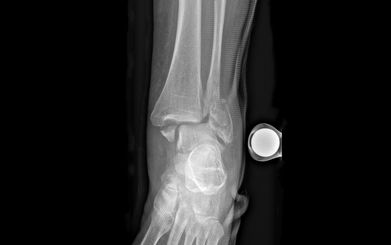

Unter einem Knöchelbruch – auch Sprunggelenkfraktur oder Malleolarfraktur – wird ein Bruch (Fraktur) des inneren und/oder äusseren Knöchels verstanden. Oft treten dabei auch Begleitschäden an Bändern, Knorpeln oder Sehnen auf.

Die Schmerzen und die Schwellung über dem Aussen- und/oder Innenknöchel lassen bei der Untersuchung häufig auf eine Bandverletzung oder einen Bruch schliessen. Die definitive Diagnose wird jedoch erst anhand eines Röntgenbilds gestellt. Eine weiterführende Diagnostik mittels Magnetresonanztomographie (MRT bzw. engl. MRI für magnetic resonance imaging) bleibt unklaren Fällen mit hohem Verdacht auf zusätzliche Syndesmosenverletzung vorbehalten. Bei komplizierten Brüchen dient eine Computertomographie (CT) der besseren Erkennung oder dazu, knöcherne Zusatzverletzungen auszuschliessen.

Verschobene Brüche sollten operiert werden, um einer späteren Arthrose vorzubeugen *. Der richtige Zeitpunkt dafür hängt jedoch vom Zustand der Weichteile ab. Diese sollten nicht zu fest angeschwollen sein, da sonst die Haut nach der Operation nicht mehr richtig verschliesst. In Fällen mit starker Schwellung und instabilen Brüchen kann auch eine externe Fixation (Fixateur externe) notwendig sein *. Nach der Weichteilkonditionierung (abschwellende Massnahme) kann dann die definitive Frakturversorgung 5 bis 10 Tage später erfolgen.